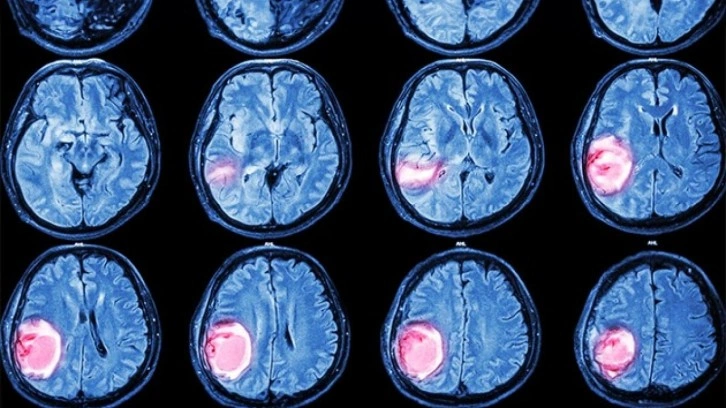

Beyin tümörlerinin belirtilerini sıralayan Dr. Gökçek, “Bulantı, kusma, baş ağrısı, baş dönmesi, sara nöbetleri, kişilik değişiklikleri, hafıza ve görme bozuklukları, anormal göz hareketleri ve kulakta çınlama beyin tümörlerinin en sık görülen belirtileri arasında” dedi. Beyin tümörlerinin kesin tanısı için MR çekiminin altını çizen Dr. Gökçek, “Kapalı alan korkusu olan hastalar için tomografi kısa sürede bilgi verebilir. Ancak beyin tümörlerinin doğru şekilde tespiti ve lokalizasyonu için MR şarttır” diye konuştu.